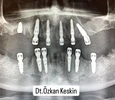

Dt.Özkan Keskin; 2013 yılında Çukurova Üniversitesi Diş Hekimliği Fakültesinden mezun olmuştur. Şu an aktif olarak Özel Dentolya Ağız ve Diş Sağlığı Merkezinde Diş Hekimliği ve Mesul Müdür olarak hastalarına hizmet vermektedir.